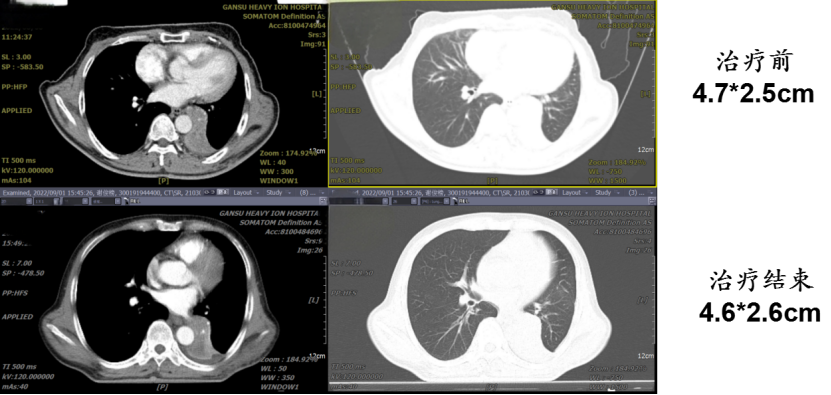

病例四:谢某某,男,65岁;入院日期:20220805,初步诊断:左肺下叶鳞状细胞癌,分期: cT2bN1M0 ⅢA期。2022年6月于华中科技大学某医院行“全麻下开胸探查术”,术中发现胸膜粘连严重、多发肺大疱、肺气肿,因肺功能极差未能切除病灶。2022年8月在我中心接受重(碳)离子治疗。重(碳)离子治疗后20月局部有肺不张和肺实变,没有肿瘤存活,随访至今,状况良好。

病例提供医生:张雁山主任 科室:放疗中心一科(国际一部)